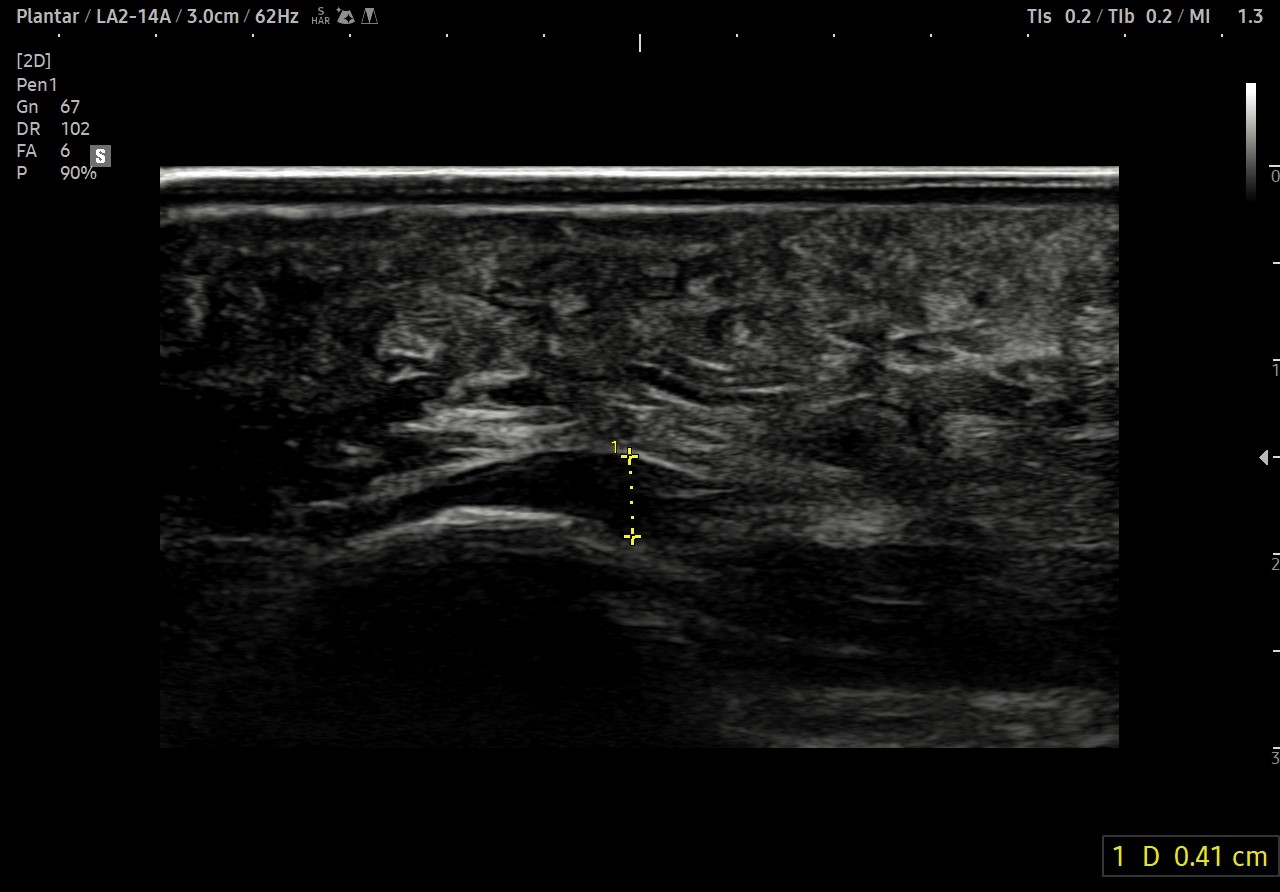

[치료전]

족저근막 두께 7mm

[치료후]

족저근막 두께 4.1mm

- 치료기간 : 2025. 8 . 9 ~ 2025 . 10 . 17

- 치료횟수 : 2cycle(9회, 증상 호전으로 치료 조기종료)